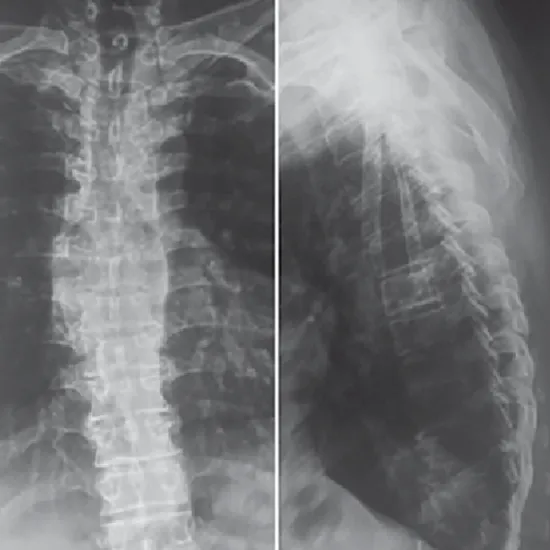

X-Ray Thoracic Lumbar (AP/LAT) View

An X-ray of the thoracic spine is an imaging exam that may detect any issues with the bones located in the center of your back. The thoracic spine x-ray images the 12 bones in our upper and middle back.